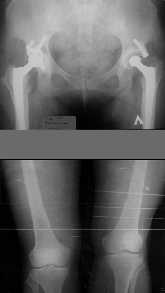

1. Иллюстрации - во вложении.

Два бедра после эндопротезирования.

Авторы операции долго думали почему больная хромает.

Сдклали снимок - одна нога короче почти на 3 см.

Здоровый человек и то будет хромать.